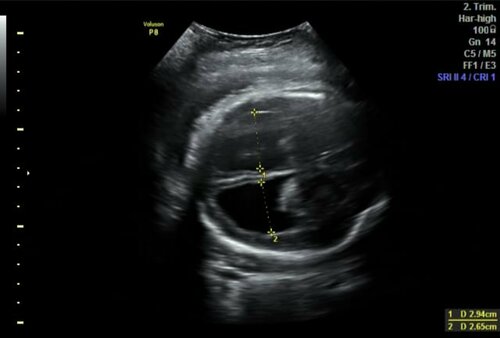

Case Study | Early Detection of Fetal Hydrocephalus | Dr. Deepti Agarwal

At GMS Mangal Diagnostics, a routine Level II Anomaly Scan revealed a critical finding: the presence of fetal hydrocephalus, characterized by an abnor...